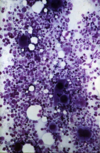

Lecture 23: Heart Vessels Blood/Microstructure, Histology Flashcards

(36 cards)

1

Q

A

band neutrophil

2

Q

A

band neutrophil